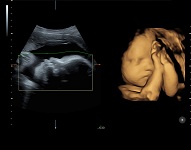

Клинические изображения VOLUSON S8